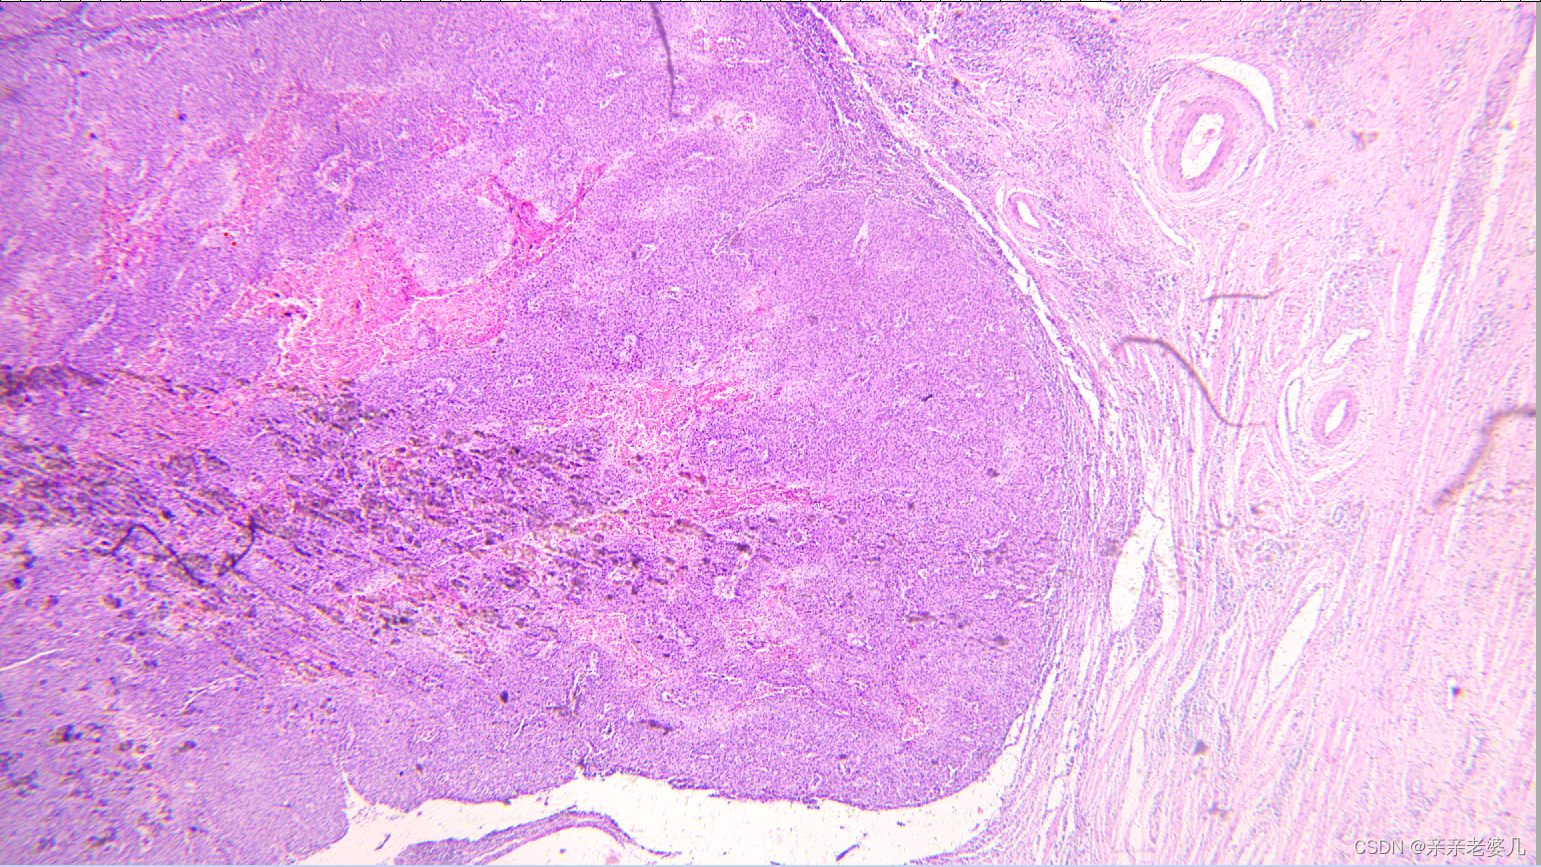

9. 千奇百怪的疾病——疾病的显微诊断及大体实物标本展示

如何获得标本:

手术 取材 包埋 蜡块 切片 染色

肝癌

正常肝